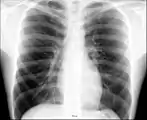

Рентгеноанатомия органов грудной клетки.

Рентгеноанатомия органов грудной клетки. Зелёным обозначены трахея и крупные бронхи, синим — ветви лёгочных артерий, красным — дуги тени сердца, цифрами отмечены сегменты лёгких.

При изучении рентгеноанатомии органов грудной клетки обращают внимание на рентгеновскую структуру видимых костей и мягких тканей грудной клетки; форму и прозрачность для рентгеновских лучей областей, на которые проецируется лёгочная ткань (так называемых «лёгочных полей»), а также их структуру, сформированную тенями сосудов лёгких («лёгочный рисунок»); расположение и структурность корней лёгких; положение, форму куполов диафрагмы и синусов плевральных полостей; форму и размеры тени средостения (в том числе сердца).

Лёгкие на рентгенограмме образуют лёгочные поля, располагающиеся по обе стороны от интенсивной тени средостения. Правое лёгочное поле короче и шире левого. В лёгочных полях различают верхушки (зоны выше ключиц), верхние отделы — от верхушек до передних отрезков вторых рёбер, средние отделы — между вторыми и четвёртыми парами рёбер, и нижние отделы — от четвёртых рёбер до диафрагмы. Лёгочные поля в норме очень светлые (тёмные на негативе) из-за высокой рентгенопроницаемости заполненной воздухом лёгочной ткани. Структура лёгочных полей называется лёгочным рисунком, анатомическим субстратом которого являются лёгочные сосуды и, в малой степени, лёгочный интерстиций. Лёгочный рисунок визуализируется в виде переплетения сосудистых теней тяжистого, округлого и овального вида, более интенсивных в местах их пересечений. В направлении от корней лёгких к периферии рисунок лёгочных сосудов становится беднее и совсем не визуализируется на расстоянии 1—1,5 см от края лёгочных полей. Лёгочный рисунок наиболее густой в нижних отделах лёгочных полей, обедняясь к верхушкам. Тени бронхов на рентгенограмме визуализируется в виде двойных полосок или колец с просветлением внутри.[3][4]

Тень корней лёгких определяется парамедиастинально на уровне передних отрезков II—IV рёбер, левый корень располагается несколько выше правого и частично скрыт тенью средостения. Ведущим анатомическим субстратом в формировании тени корней лёгких являются лёгочные артерии и бронхи, в меньшей степени — лёгочные вены и другие структуры. В норме корни лёгких имеют неоднородное изображение, представляя собой структурированную совокупность элементов различной плотности. В корнях лёгких различают головку, тело и хвост. Правый корень визуализируется на всём протяжении в виде лентовидной, суживающейся книзу изогнутой тени средней интенсивности, отделённой от тени сердца промежуточным и нижнедолевым бронхами. К периферии от корней лёгких отходят лёгочные сосуды, причём артериальные ветви имеют более вертикальное направление, венозные — более горизонтальное. Ширина корня лёгкого соответствует ширине его основного артериального ствола; в норме она равна ширине бронха, отделяющего корень от средостения, и не превышает 1,5 см.[3][4]

Сердечно-сосудистая тень занимает центральное положение на рентгенограмме органов грудной клетки. На рентгенограмме в прямой проекции её контуры в норме формируют две дуги справа и четыре — слева. Нижняя дуга правого контура образована правым предсердием, верхняя, более медиальная — восходящей частью аорты и верхней полой веной. Первая (верхняя) левая дуга образована дугой и начальным отделом нисходящей аорты, вторая — лёгочным стволом, третья — ушком левого предсердия, четвёртая — левым желудочком. В области второй и третьей дуг контур тени средостения вогнут и носит на этом уровне название «талия сердца»; эта зона является границей между сердцем и связанными с ним сосудами.[5]